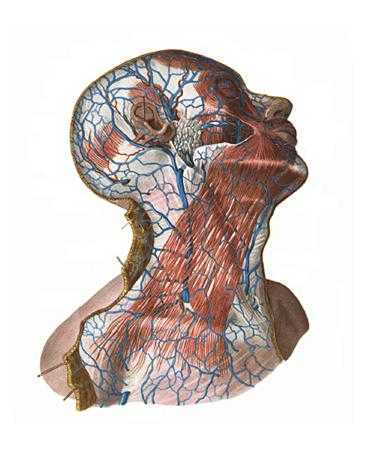

Анатомия внутренней яремной вены: КТ изображения